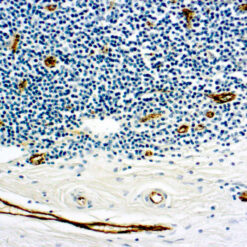

Calponin-1

Multiple isoelectric variants of calponin have been identified but only two molecular weight isoforms exist (34kDa and 29kDa). Expression of the 29kDa form, I-calponin, is primarily restricted to muscle of the urogenital tract, whereas the higher molecular weight variant has been demonstrated in vascular and visceral smooth muscle. Calponin is a calmodulin, F-actin and tropomyosin binding protein, which is thought to be involved in the regulation of smooth muscle contraction. Calponin expression is restricted to smooth muscle cells and has been shown to be a marker of the differentiated (contractile) phenotype of developing smooth muscle.

| Positive Control Tissue | Uterus |